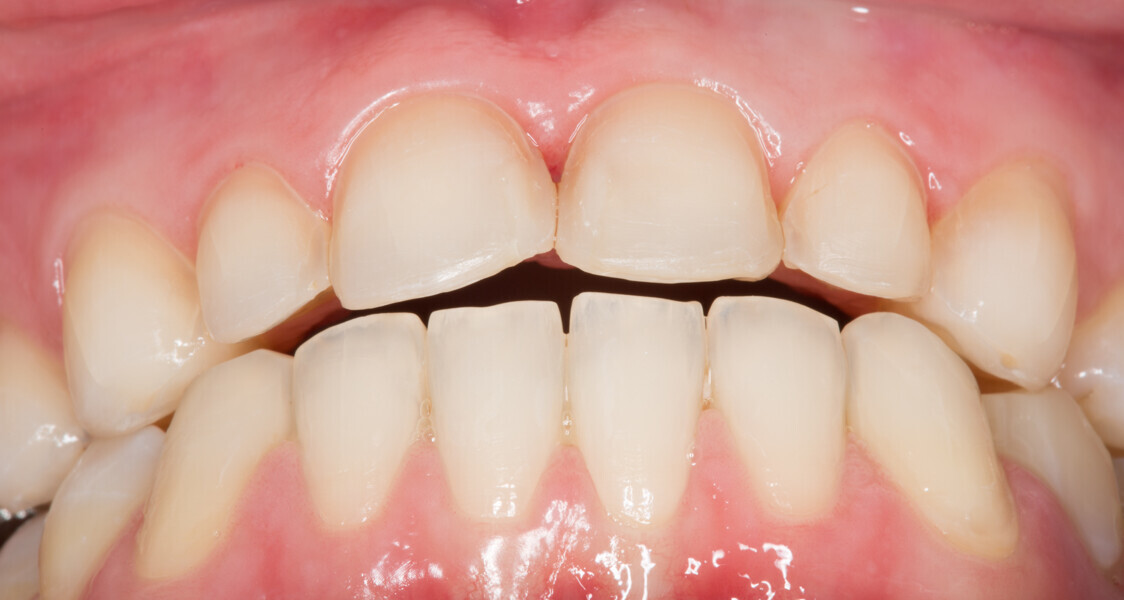

Fig. 1: Initial clinical situation.